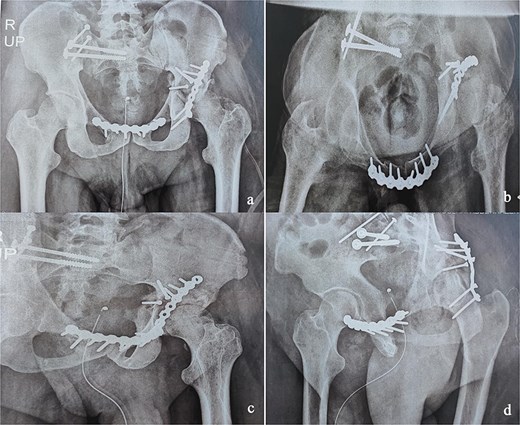

This was a 42-year-old male patient with no previous medical history who was admitted to the intensive care unit for treatment of polytrauma: severe chest trauma and pelvic trauma. During his stay in intensive care, the patient developed a pulmonary infection complicated by septicemia, requiring prolonged antibiotic therapy and thereby contraindicating any internal surgical fixation. After hemodynamic and respiratory stabilization, he was transferred to our department 40 days after the trauma with the following injuries: an unstable pelvic ring fracture classified as Tile-AO B1-2 [4]: disjunction of the pubic symphysis, disjunction of the right sacroiliac joint, and an ipsilateral crescent fracture classified as Kumar-Day 2 [5], along with a transverse–posterior wall fracture of the left acetabulum associated with a posterior dislocation of the hip, which was initially reduced but remained unstable. Fixation was performed using a Hoffmann II external fixator applied to the iliac crests with poor reduction (Fig. 1). He presented with complete weakness of the left foot dorsiflexors, with preserved sensation and no urogenital or abdominal complications. ORIF was performed in two stages, 5 days apart. The first stage consisted of performing the first two windows of the ilioinguinal approach: the lateral window to access the sacroiliac joint and the middle window to access the lower part of the sacroiliac joint and remove the osteofibrous callus. A Pfannenstiel approach was used to remove the callus at the pubic symphysis and fix it with a plate. The patient was then placed in the prone position and a posterior approach to the right sacroiliac joint was performed to carry out the same procedures on the posterior part of this joint and to perform fixation using ilioiliac and iliosacral screws. The second stage of the operation involved acetabular surgery. Given the chronic dislocation of the left hip, an anterior approach to the hip was performed to remove the intra-articular fibrosis facilitating the subsequent reduction of the femoral head. A Kocher-Langenbeck approach was then performed to remove the callus, reduce the femoral head and fracture, and fix it with a plate (Fig. 2). Postoperatively, the patient retained neurological deficits. At 6 months, the patient was able to walk without assistance and had a Harris Hip Score (HHS) score of 80 and Majeed score of 75 [6, 7].

Immediate postoperative X-rays. (a) Anteroposterior pelvic X-ray. (b) Inlet view of the pelvis. (c) Alar oblique view of the pelvis. (d) Obturator oblique view of the pelvis.